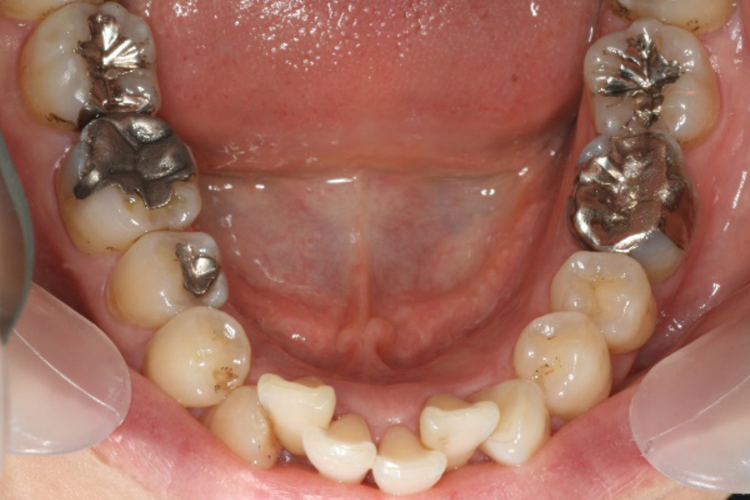

奥歯(臼歯)